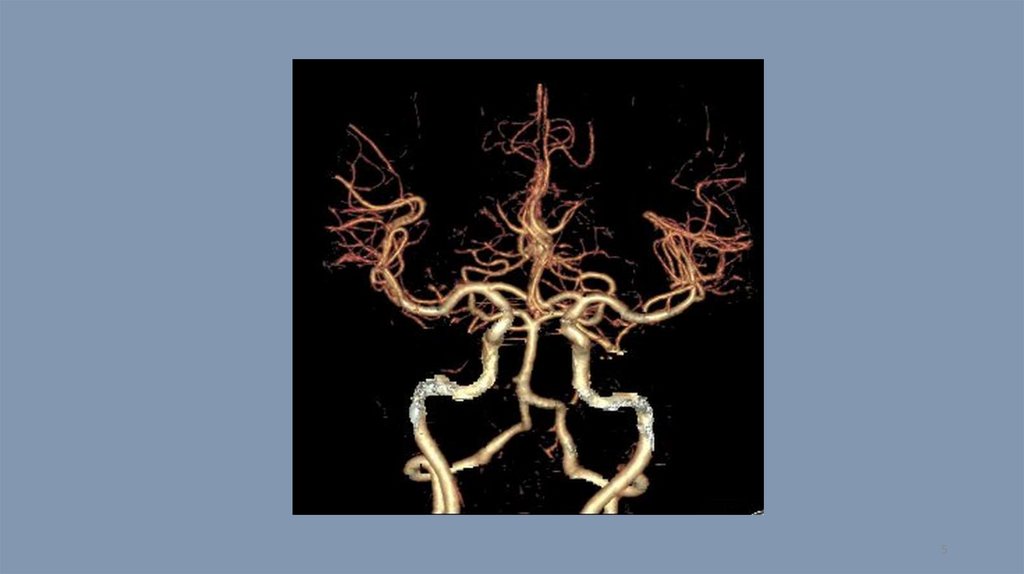

Компьютерная томография. Тест 14